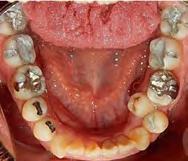

Estudios de inicio fotografías intraorales

En la Figura 3 se muesta clase III molar y canina, el overjet y overbite negativos, en la Figura 4 las líneas medias coincidentes, la mordida abierta anterior, en la Figura 5 la clase III molar y canina, overjet y overbite negativos, en la figura 6 se ven formas de los arcos ovales, el apiñamiento severo superior e inferior.

Figura 3. Lateral derecha. Figura 4. Frente intraoral. Figura 5. Lateral izquierda. Figura 6. Intraorales oclusales.